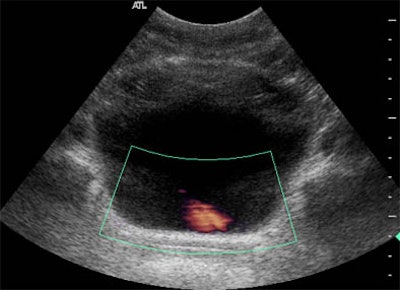

Video 3: A fragment of the remotely guided imaging on orbit demonstrating a ureteral jet on the left side; urine (pink) seen in Doppler US flows from the ureter into the bladder. This exam assumes more importance in space as ultrasound is the sole modality available to assess ureteral patency. On the audio track, Sargsyan directs the exam remotely from Houston to the ISS.

![]() |

| Remotely guided Doppler ultrasound of the left ureter shows urine flow (pink) into the bladder. |